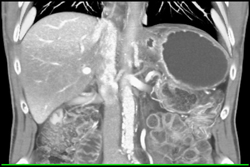

Hemangioma Simulates An Arterial Phase Imaging and Gastric Duplication